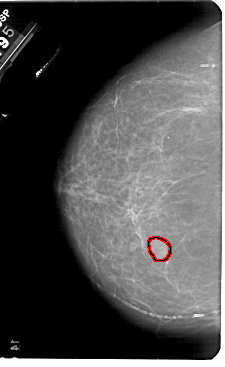

A_1836_1.LEFT_CC

LEFT_CC LINES 5491 PIXELS_PER_LINE 3361 BITS_PER_PIXEL 12 RESOLUTION 43.5 OVERLAY

FILE: A_1836_1.LEFT_CC.OVERLAY

TOTAL_ABNORMALITIES 1

ABNORMALITY 1

LESION_TYPE MASS SHAPE OVAL MARGINS OBSCURED

ASSESSMENT 3

SUBTLETY 5

PATHOLOGY BENIGN

TOTAL_OUTLINES 1